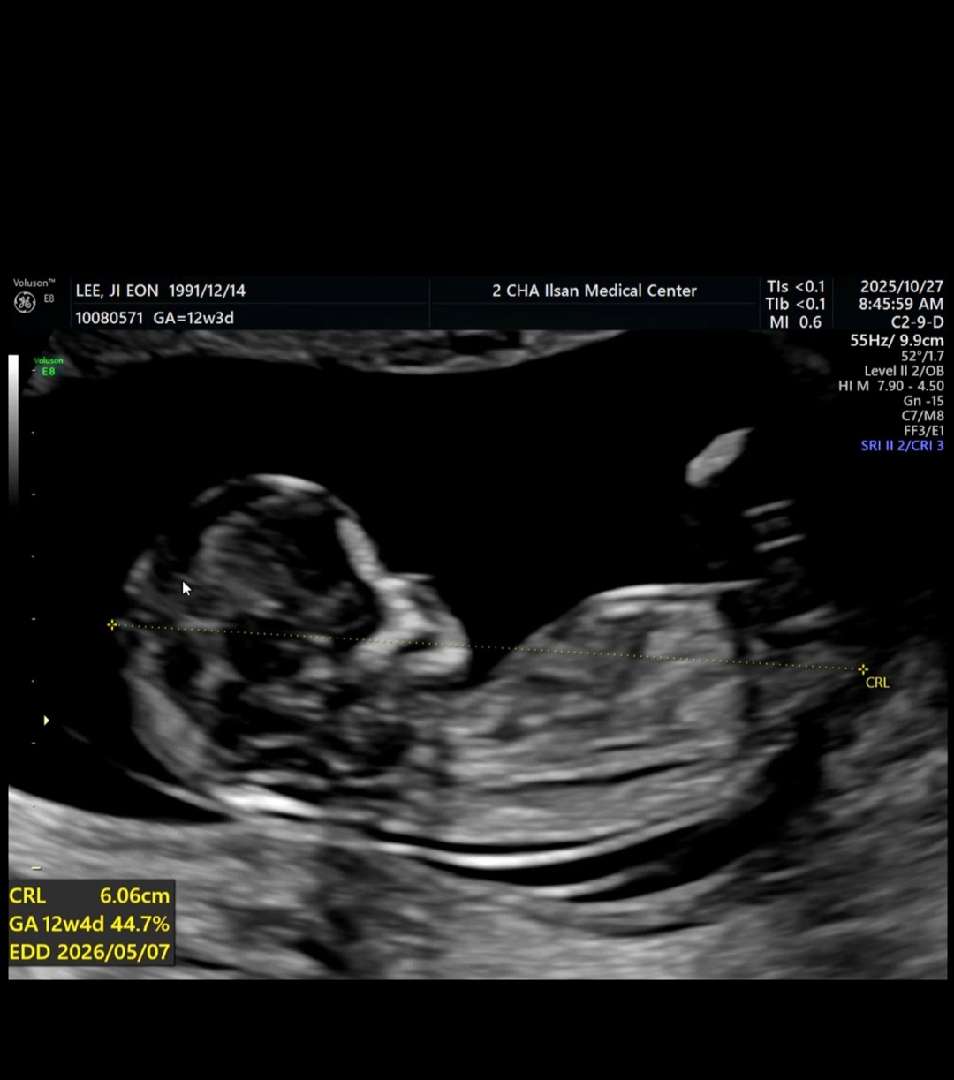

각도법 부탁드려요~~ 12주입니다

참견 많이부탁드립니다 너무궁금해요~~